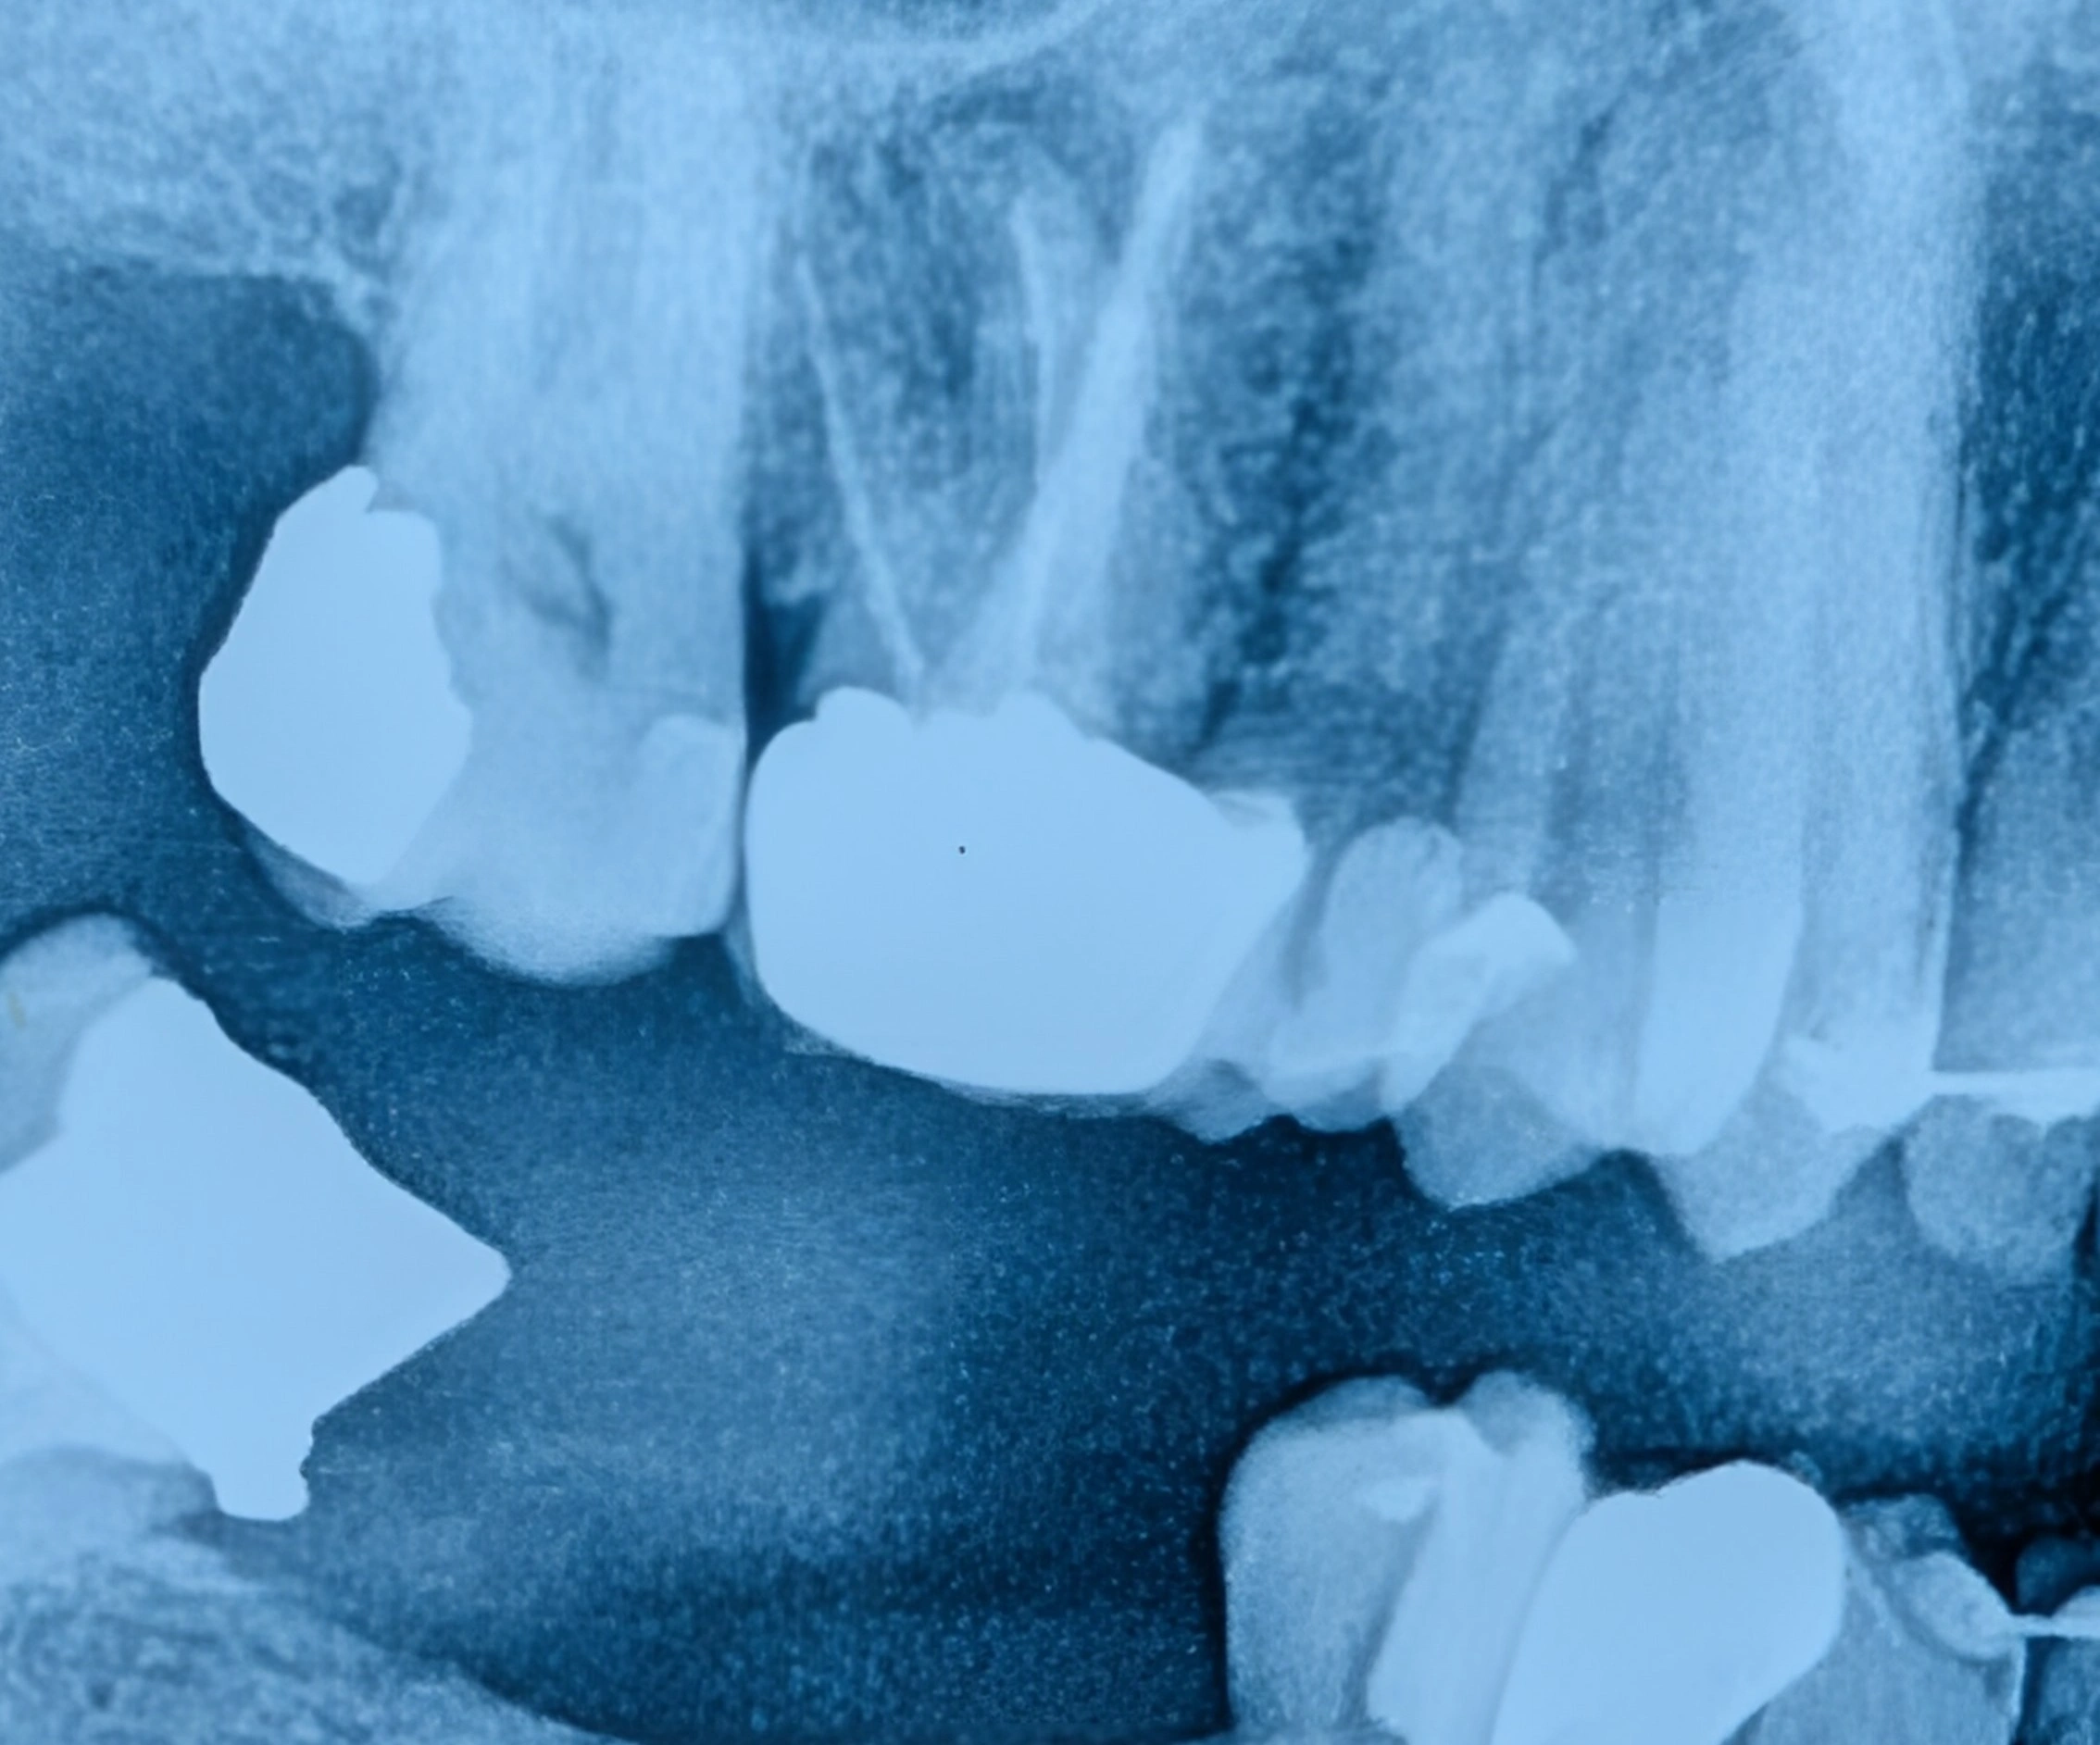

عکس پانورامیک دندان‌ها (OPG)

نمای کلی فک‌ها و دندان‌ها در عکس پانورامیک (OPG)

عکس پانورامیک نمای کلی از فک‌ها، مفاصل و موقعیت دندان‌ها را نشان می‌دهد و برای بررسی وضعیت عمومی دهان بسیار مفید است.

با این حال، به دلیل بزرگ‌نمایی تصویر و کاهش وضوح جزئیات، پوسیدگی‌های کوچک یا بین دندانی در این تصویر به‌خوبی دیده نمی‌شوند.